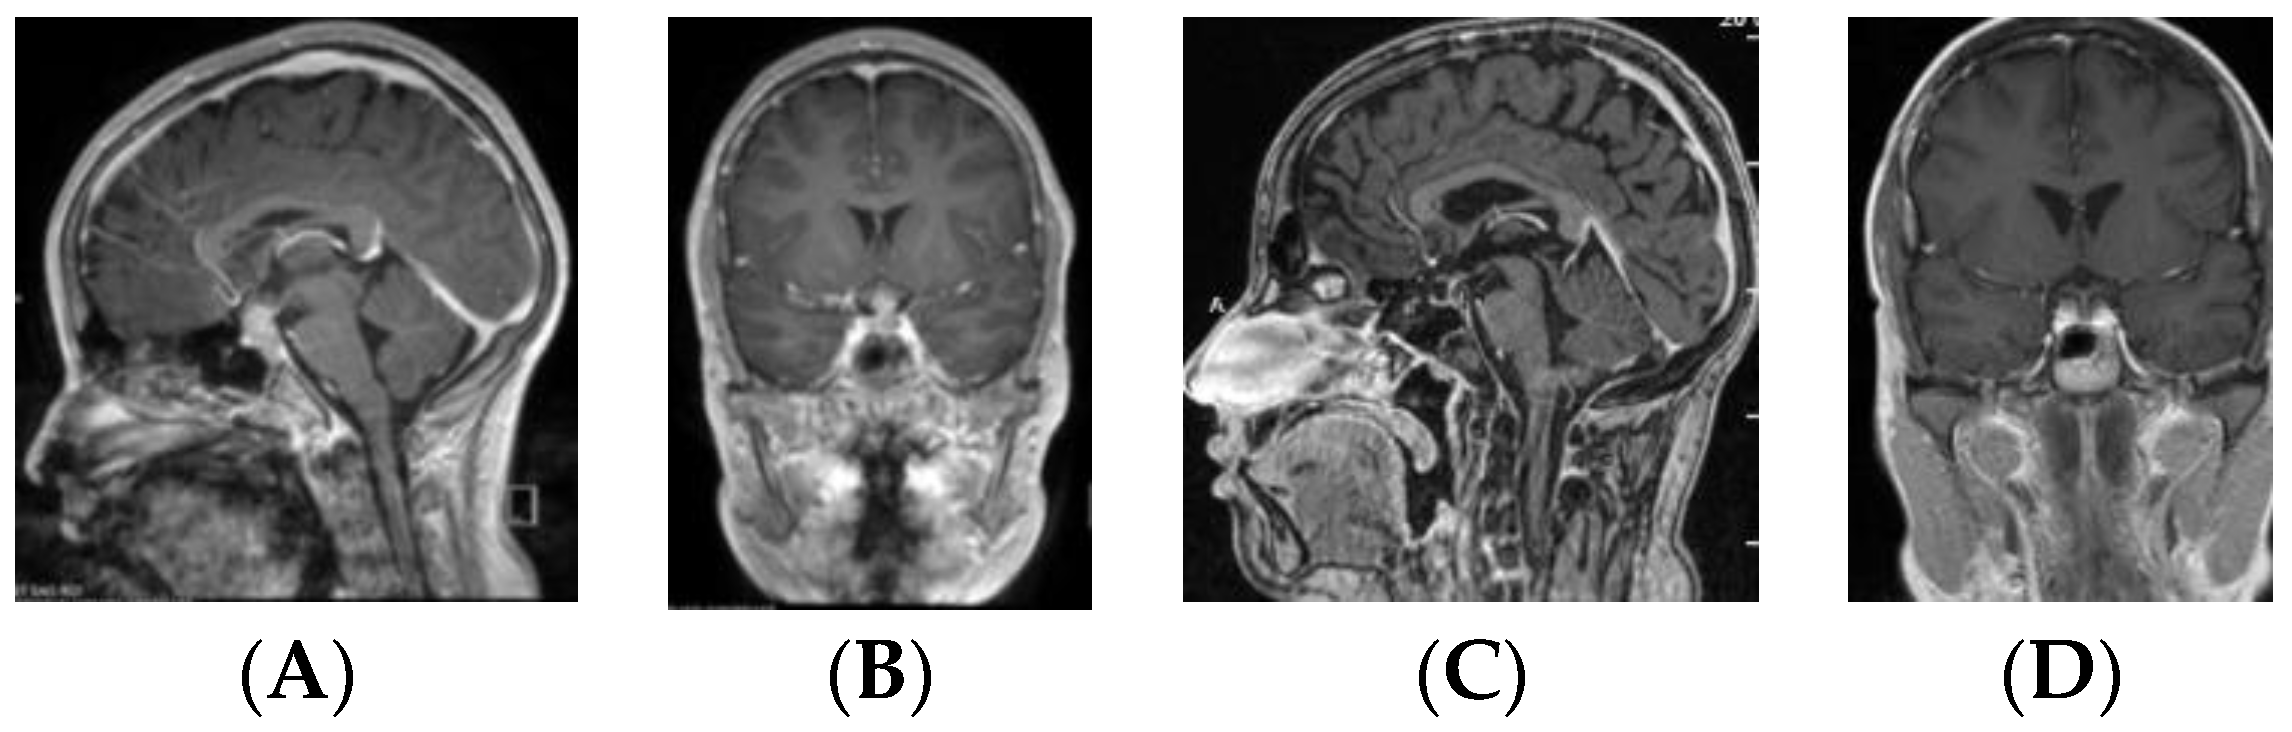

• Type IV: Small laminar (L) or nodular (N) lesion at the floor of III ventricle extending to upper PS (Figure 5);

• Type V: Limited to the PS (Figure 6).

Figure 5. Type IV. Post-contrast MR, sagittal (A) and coronal (B) views of a patient with bifocal germ cell tumor (GCT). Note a laminar tumor at the floor of the third ventricle with upper pituitary stalk involvement. Post-contrast MR, sagittal (C) and coronal (D) views of a patient with bifocal GCT with a nodular tumor at the floor of the third ventricle with upper pituitary stalk involvement.

By contrast, the majority (11/16, 68.8%) of bifocal GCTs were smaller and Type IV (Figure 5). These tumors were accompanied by much larger pineal region tumors. Four bifocal tumors were Type Ia or Type Ib tumors with similarly sized globular masses in the suprasellar and pineal regions. 1 patient had a Type II mass with extension of the tumor directly into the sella turcica.